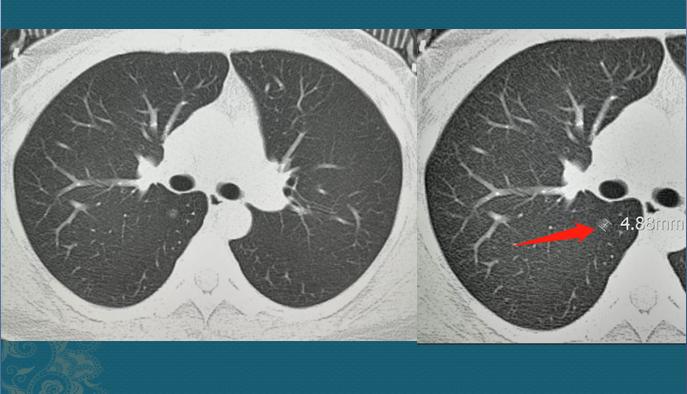

这是2016年的肺部CT,箭头所指,右下肺背段一个纯磨玻璃小结节,边界比较清,直径4.8mm。不足5mm的纯磨玻璃结节属于低危结节,大部分多年不变化,有些炎性结节会自动消失,不需要处理,随访观察就好!